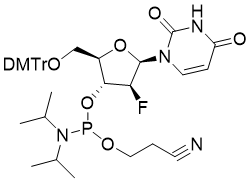

馬鞍山致研生物醫(yī)藥科技有限公司成立于馬鞍山市鄭浦港新區(qū)現(xiàn)代產(chǎn)業(yè)園。公司專(zhuān)注于生物小分子、醫(yī)藥中間體相關(guān)產(chǎn)品的研發(fā)和生產(chǎn),產(chǎn)品主要包括DNA亞磷酰胺單體、RNA亞磷酰胺單體、特殊單體以及按照客戶(hù)要求定制的RNA和DNA,并且公司提供定制合成等方面的研究服...

馬鞍山致研生物醫(yī)藥科技有限公司成立于馬鞍山市鄭浦港新區(qū)現(xiàn)代產(chǎn)業(yè)園。公司專(zhuān)注于生物小分子、醫(yī)藥中間體相關(guān)產(chǎn)品的研發(fā)和生產(chǎn),產(chǎn)品主要包括DNA亞磷酰胺單體、RNA亞磷酰胺單體、特殊單體以及按照客戶(hù)要求定制的RNA和DNA,并且公司提供定制合成等方面的研究服...